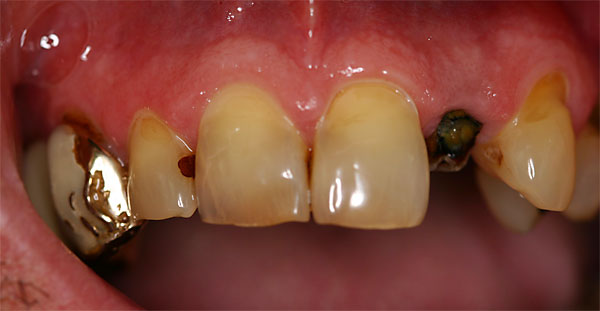

Fall: Von der Prothese zur fixen Krone